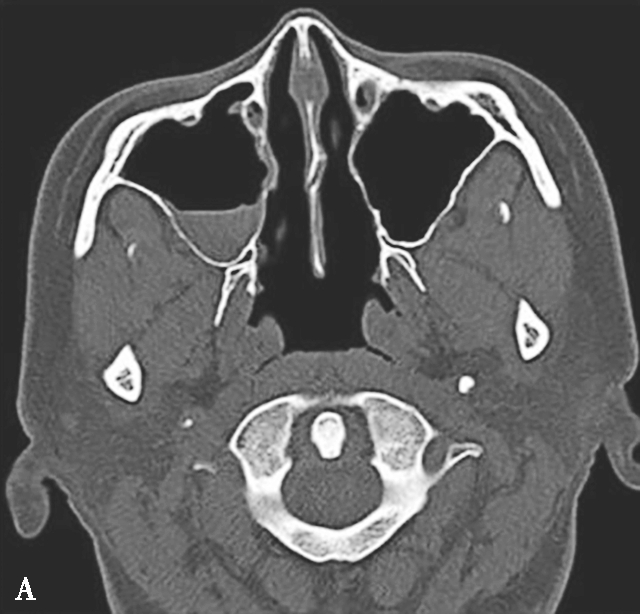

图1-3-26 鼻腔鼻窦肉芽肿性多血管炎

A、B.横断面CT及冠状面CT骨窗,示鼻背部塌陷,鼻中隔、双侧筛窦及上颌窦黏膜增厚,窦壁骨质增生硬化,内缘骨皮质欠光整;双侧中、下鼻甲形态欠自然,双侧眼眶内下壁骨皮质部分缺损,邻近内下象限肌锥外间隙可见弥漫性软组织增厚影,右侧为著;双侧上颌窦口-鼻道复合体增宽,钩突缺如;C.横断面T 1 WI,示双侧上颌窦腔可见略低信号,气-液平面可见,鼻背部塌陷,鼻中隔黏膜增厚,鼻咽顶后壁软组织增厚,呈等信号;D.横断面T 2 WI,示上颌窦腔病变呈高信号,余病变呈略低信号;E.横断面T 1 WI+FS+C,示窦腔、鼻中隔增厚,黏膜及其他受累结构呈中等强化,双侧翼腭窝及上颌窦后脂肪间隙受累,强化;F.冠状面T 1 WI+FS+C,示双侧眼眶内下象限肌锥外间隙病变呈中等强化,大脑纵裂及额部脑膜受累,呈弥漫性增厚强化